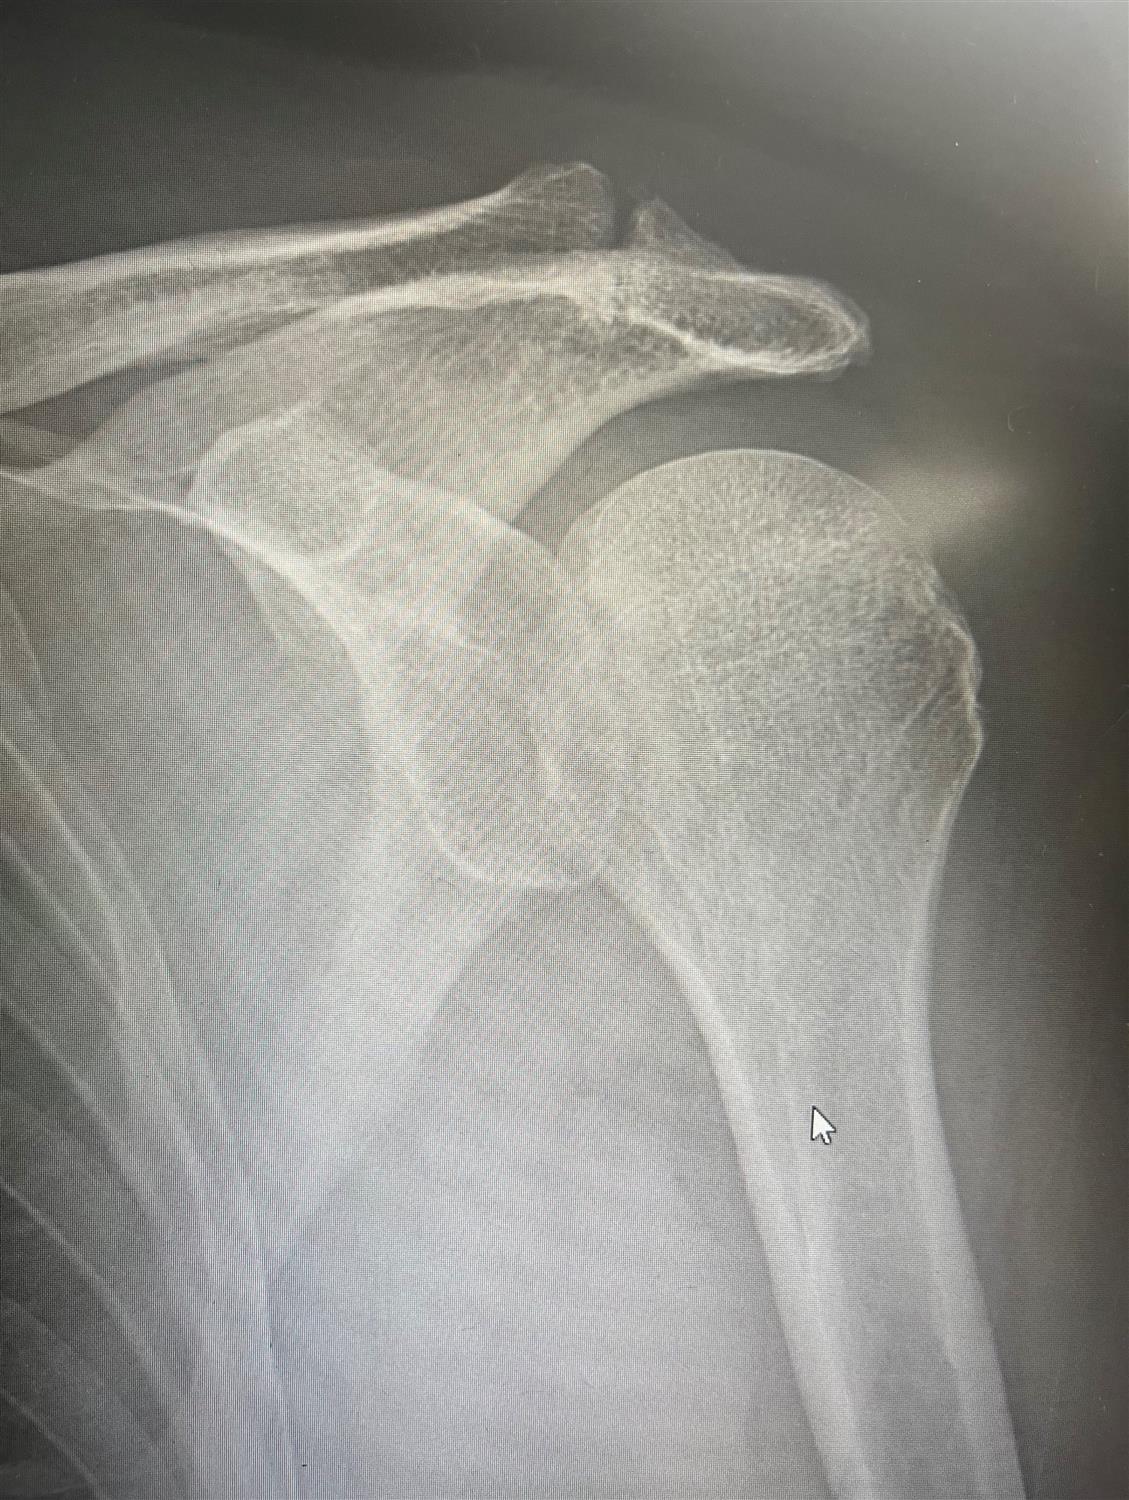

• We prospectively captured all traumatic shoulder instability events at the United States Military Academy between September 1, 2004, and May 31, 2005. Throughout this period, all new traumatic shoulder instability events were evaluated with physical examination, plain radiographs, and magnetic resonance imaging. Instability events were classified according to direction, chronicity, and type (subluxation or dislocation). Subject demographics, mechanism of injury, and sport were evaluated.